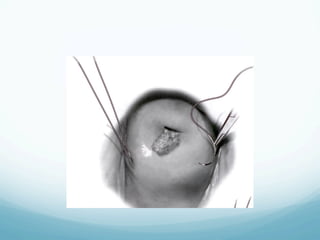

Sharp Conization

—  One of the oldest techniques

—  Recommended for women with suspected

microinvasion and AIS

—  The margins of the cone are plotted colposcopically

using acetic acid or Lugol s solution

—  The configuration of the specimen is based on the

extent of disease

—  Complications include: bleeding (immediate or

delayed), cervical stenosis, cervical incompetence

Sharp Conization —  Oneof the oldest techniques —  Recommended for women with suspected microinvasion and AIS —  The margins of the cone are plotted colposcopically using acetic acid or Lugol s solution —  The configuration of the specimen is based on the extent of disease —  Complications include: bleeding (immediate or delayed), cervical stenosis, cervical incompetence